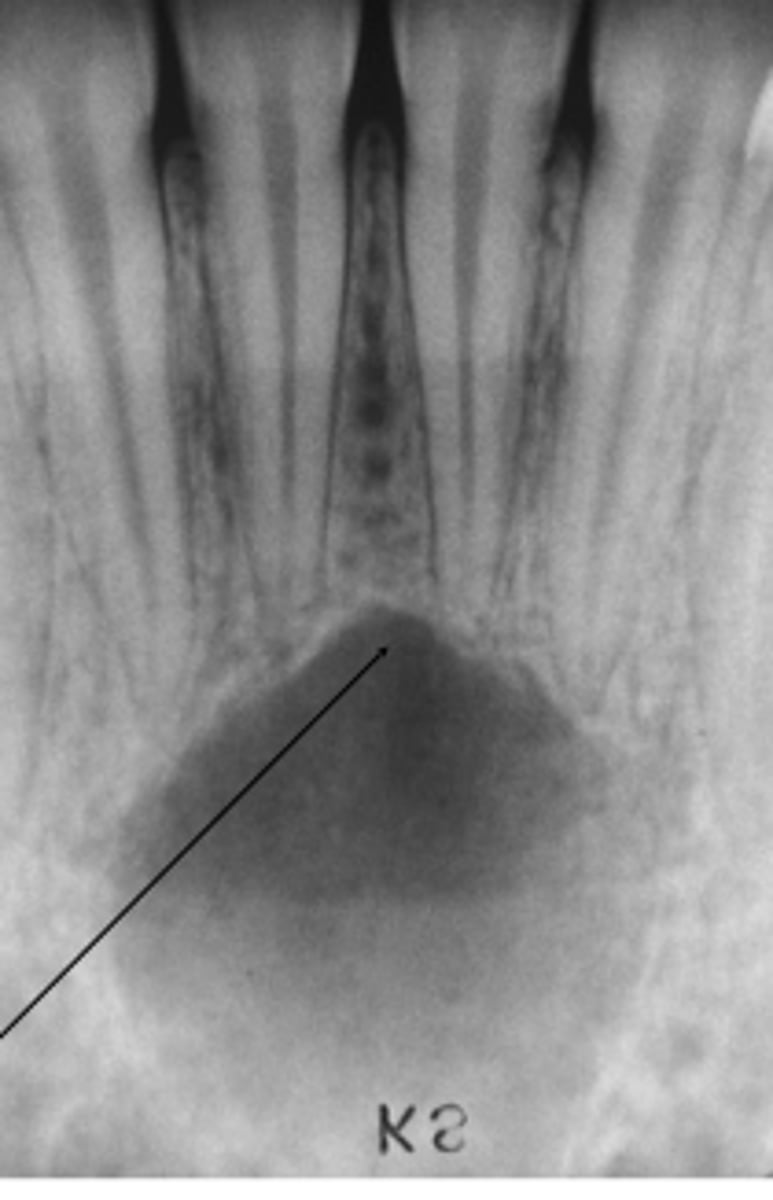

Empty or fluid-containing bone cavity

Pseudocyst (lacks epithelial lining)

Where does simple bone cysts typically occour?

Marked mandibular predominance

What is a clinical manifestation associated with simple bone cysts?

20% of patients present painless jaw swelling

Jaw lesions are normally asymptomatic.

diagnosed by radiographic examination.

what is the diagnosis for simple bone cyst?

Radiographic signs are not specific

• Surgical exploration is required